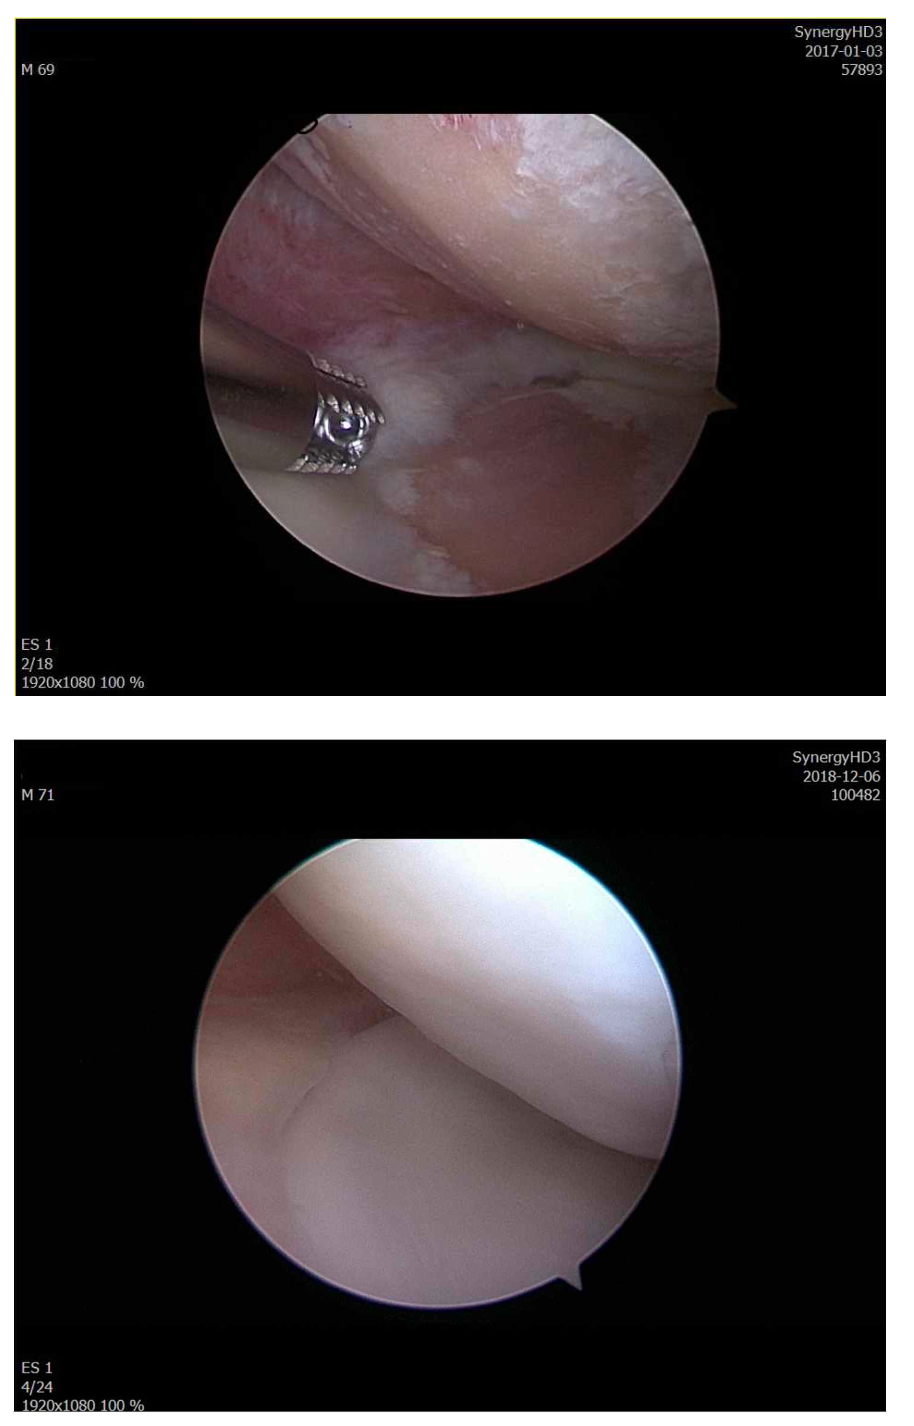

Arthroscopic Surgery

- Arthroscopic cartilage repair

- Meniscal repair

- Ligament reconstruction

- High success rates in active patients and athletes

Participants observe and engage in real-world procedures used to repair complex cartilage defects that cannot be adequately treated with conventional methods.

Emphasis is placed on restoring hyaline-like cartilage, optimizing long-term joint function, and minimizing the need for joint replacement.